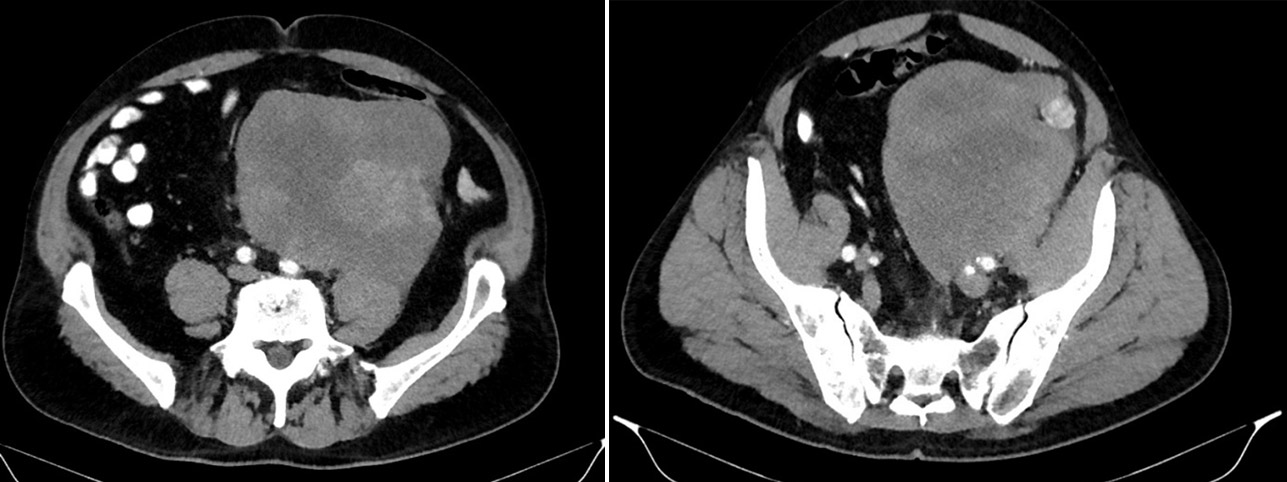

Intravenous contrast CT: in the in the mesohypograstral region on the left, with spread into the pelvic cavity, a massive multinodular formation of a heterogeneous soft tissue structure is determined due to areas of low density (necrosis) and high-density inclusions (hemorrhagic), with unclear tuberous contours, measuring 14×15×16 cm (Fig. 1).

Figure 1. CT scans before surgery.

The tumor is closely adjacent to the left lumbar and lumboiliac muscles over a large area, without a clear border on individual sections; it involves the left ureter in its middle and lower thirds; it infiltrates the infrarenal segment of the abdominal aorta, the left common and external iliac arteries; it is partially adjacent to the sigmoid colon and the apex of the urinary bladder. According to the endoscopy data (colonoscopy and cystoscopy), no extension to the intestine and urinary bladder was found.